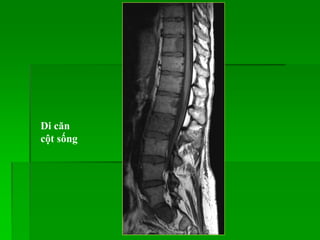

Di căn

• 4 dạng di căn cột sống:

- Hủy xương khu trú: tín hiệu thấp trên T1W, T2W

- Xơ xương khu trú: tín hiệu thấp trên T1W, T2W

- Tổn thương không đồng nhất, lan tỏa: tín hiệu thấp trên T1W, T2W

- Tổn thương đồng nhất, lan tỏa: tín hiệu thấp trên T1W, T2W

• Mức độ bắt Gd thay đổi.

Di căn thân sống và tủy sống

cột sống